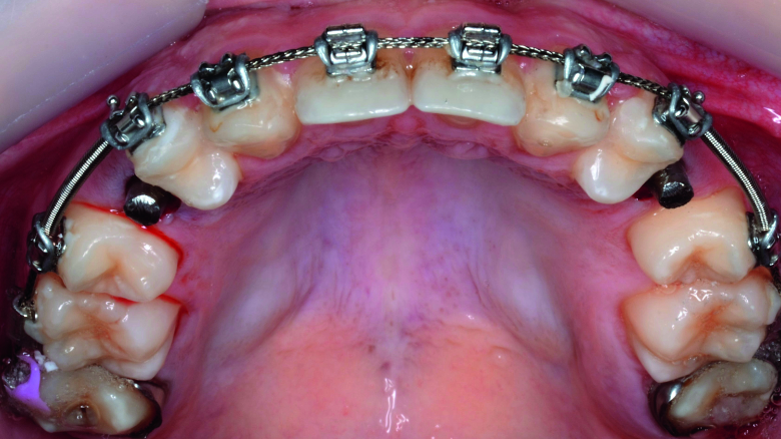

Then occlusal analysis (Figs. 11–21) was performed:

- Upper spacing due to the laterals agenesis (Fig. 18).

- Implants space opening: substitute laterals with canines (Figs. 23–25) and substitute canines with first premolars (Figs. 26–28).